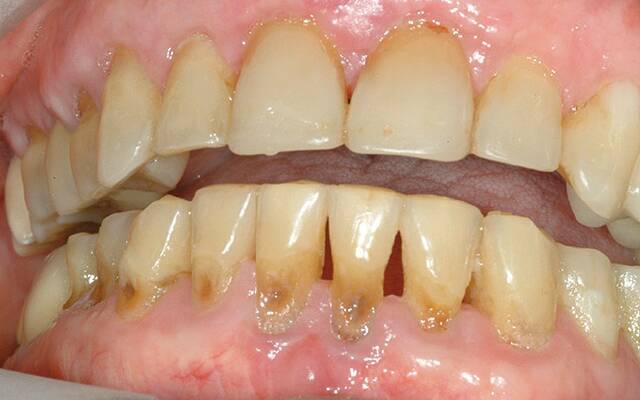

Одной из самых распространенных стоматологических болезней является прикорневой кариес, который поражает зубные ткани у корня, на границе зуба с десной, и даже может выходить за пределы коронковой части. Разрушительный процесс в этой зоне обычно развивается весьма стремительно, поскольку эмаль здесь имеет минимальную толщину: воспаление быстро проникает в глубинные слои зуба, затрагивая корневые каналы.

• образование полости на границе с десной.

Для глубокого прикорневого кариеса характеры резкие или ноющие боли при чистке зубов, перепадах температур, приеме кислой либо сладкой пищи. Однако если пораженным оказывается депульпированный зуб, болевых ощущений не будет. В таких случаях при отсутствии своевременного лечения прикорневого кариеса разрушительный процесс может привести к отлому коронковой части зуба.